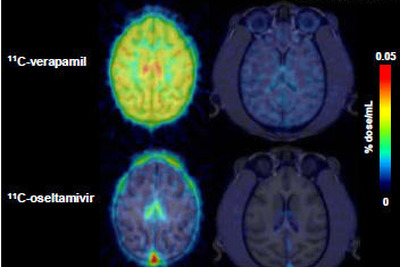

子どもの脳はタミフルの影響を受けやすい…理研ら確認

血中の異物や薬物から脳を守る機能は成長とともに発達し、幼少期には脳に取り込まれやすい薬物が存在することを、理化学研究所らが世界で初めて霊長類で確認した。